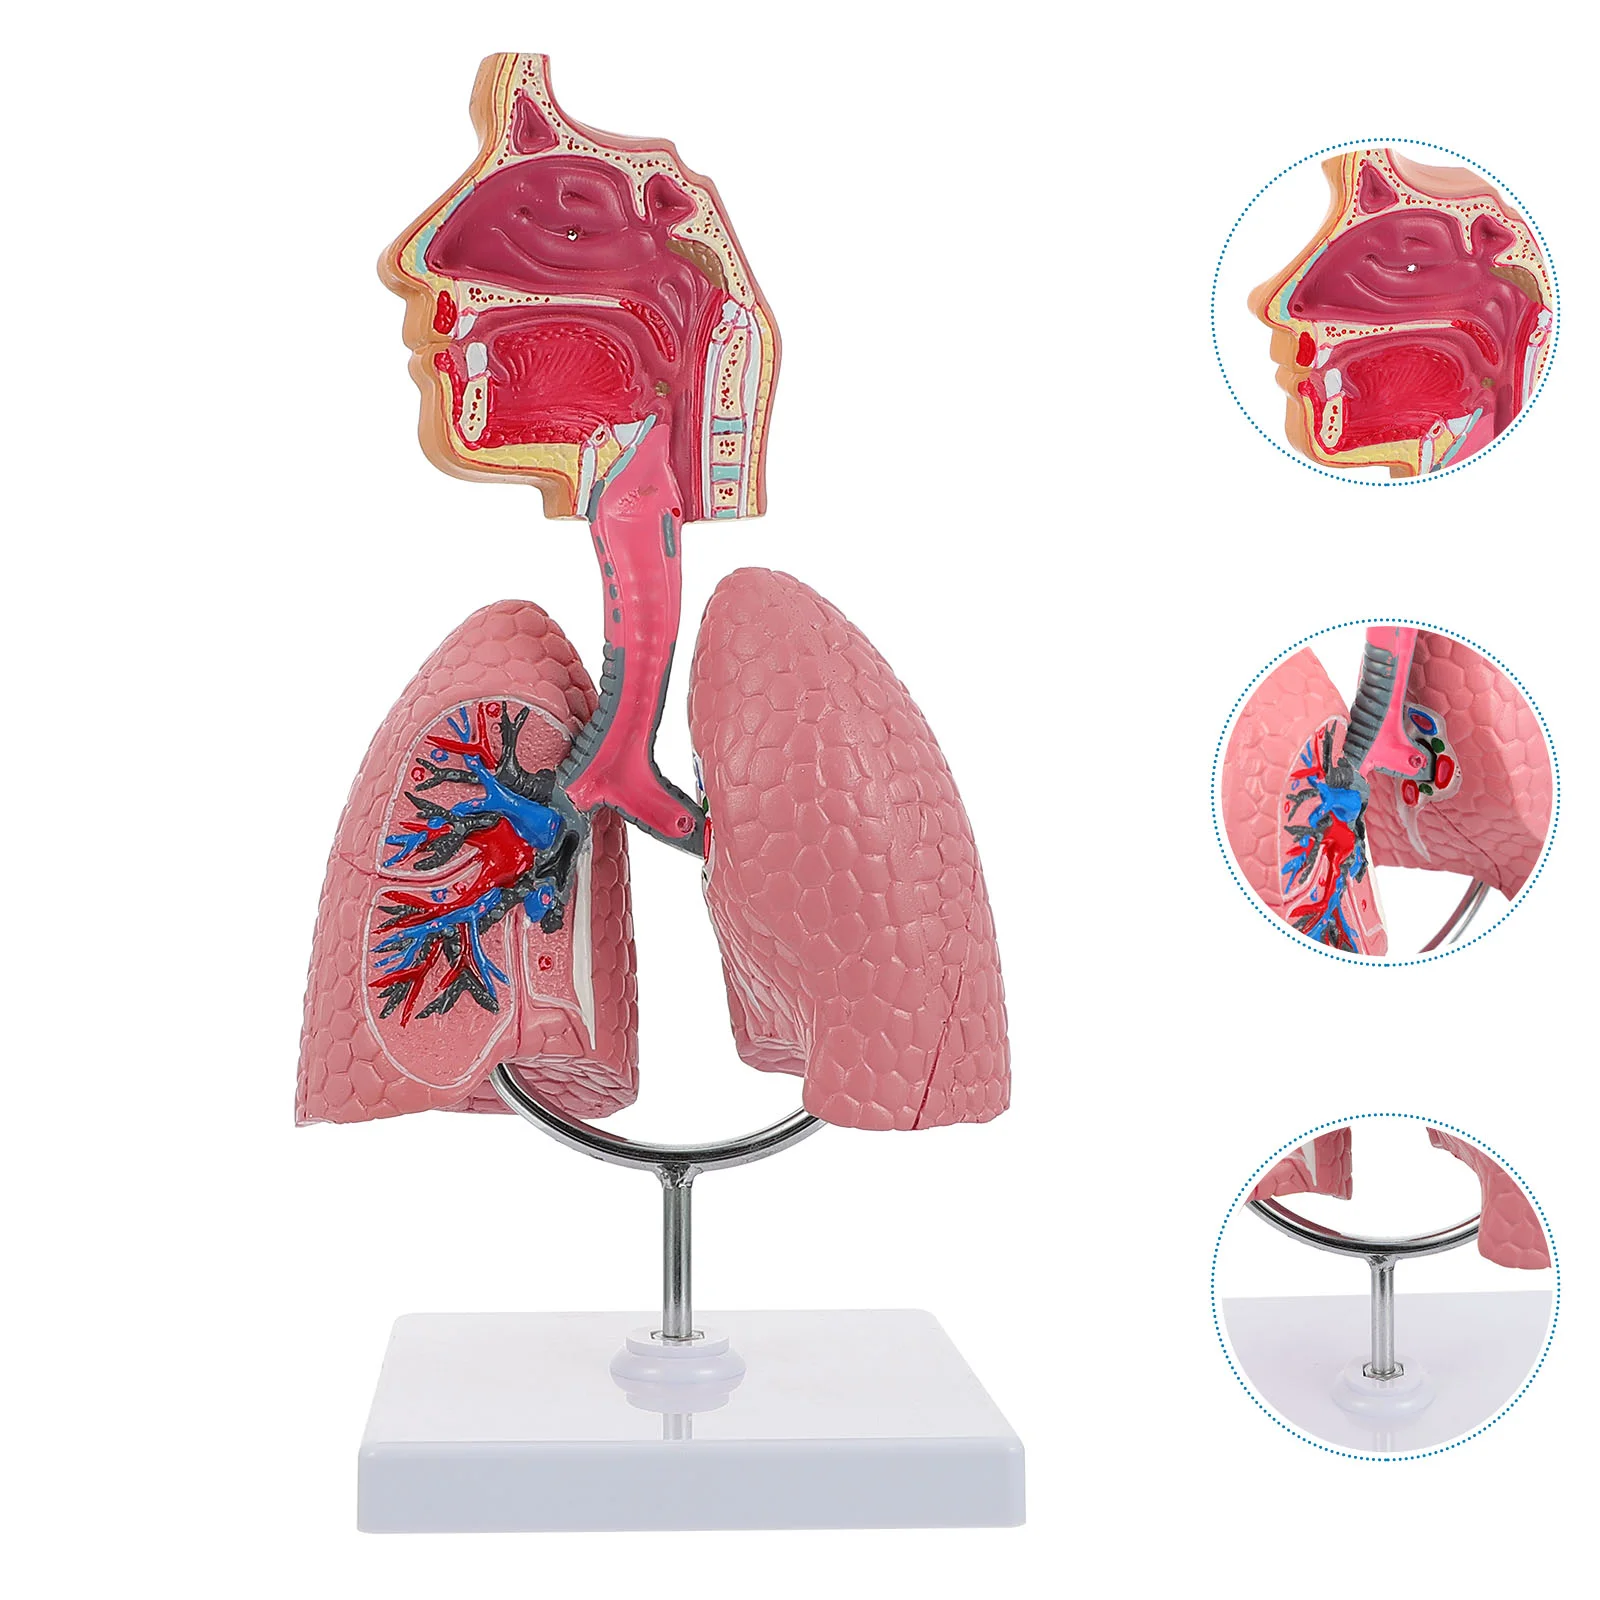

Lung Respiratory Anatomy Model Teaching System Human Display model School Lungs Anatomical Heart Educational Nasal Toy

Купить за 25305.55 RUR

Следите за акциями и распродажами в июле 2026 от aliexpress.com/..

Lung Respiratory Anatomy Model Teaching System Human Display model School Lungs Anatomical Heart Educational Nasal Toy

Купить за 25270.74 RUR

Следите за акциями и распродажами в июле 2026 от aliexpress.com/..

Lung Respiratory Anatomy Model Teaching System Human Display model School Lungs Anatomical Heart Educational Nasal Toy

Купить за 21998.45 RUR

Следите за акциями и распродажами в июле 2026 от aliexpress.com/..

Lung Respiratory Anatomy Model Teaching System Human Display model School Lungs Anatomical Heart Educational Nasal Toy

Купить за 20234.81 RUR

Следите за акциями и распродажами в июле 2026 от aliexpress.com/..

PVC Respiratory System Model Lifelike Teaching Aid for Medical Schools Anatomy Education Practical Human Lung Display Tool

Купить за 8578.06 RUR

Следите за акциями и распродажами в июле 2026 от aliexpress.com/..